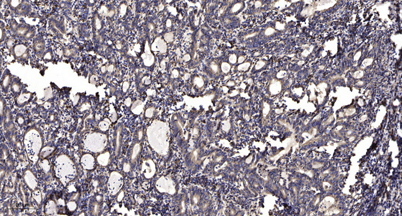

| Dilutions: | Western Blot: 1/500 - 1/2000. Immunohistochemistry: 1/100 - 1/300. ELISA: 1/20000. Not yet tested in other applications. |